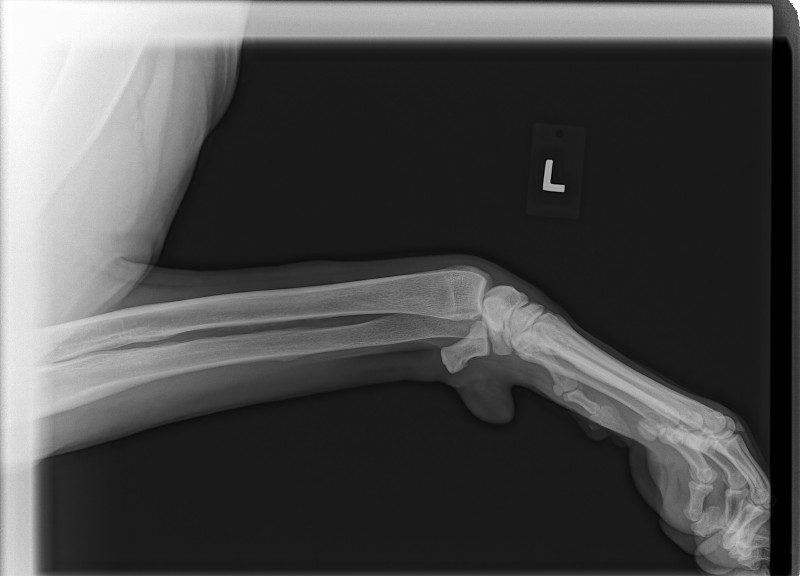

Sean has been diagnosed with a retro-peritoneal liposarcoma.

The current size of his mass is 8.2 cm x 10 cm x 21 cm. This is an extremely RARE cancer – less than 1%.

To further complicate matters, this mass has herniated down into his thigh and groin severely compromising his ureter and femoral nerve. He has had three CT scans of which his latest has shown that to date his chest remains clear of metastasis and his lymph nodes are not enlarged. His MRI has shown that his case is extremely complicated and the surgery he shall specifically require, scheduled for March 23rd has ONLY ever been done twice before by the two expert surgical oncologists assigned to him.